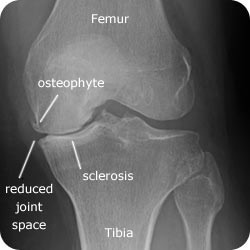

X-Ray (LOSS)